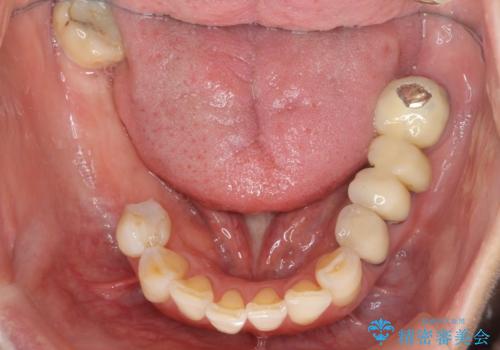

- 長年悩んでいる歯の見た目や欠損を全て治療したい、と希望され来院されました。

不適合やすり減ったクラウンを全て除去し、虫歯を丁寧に除去したのち精密なセラミック治療を行いました。

また失ってしまった奥歯についてはインプラントを用いて噛み合わせを確立する治療方針としました。